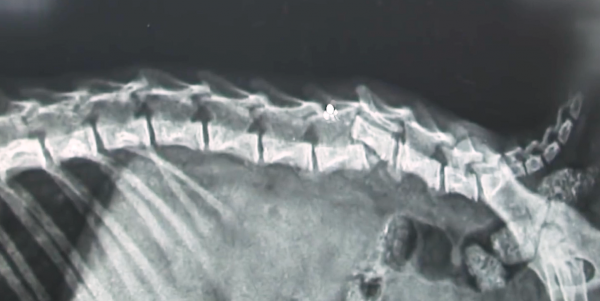

在寵物醫院裡一生仔細檢查了小貓的傷勢,發現它的下半身脊柱錯位,進而導致兩條後腿失去知覺。並且透過檢查報告可以判斷,這個傷勢是從特定的角度撞擊才會形成。所以醫生根據經驗分析,小貓身上的傷應該不是意外導致,更像是人為的虐待行為。

但是由於受傷位置特殊,小貓脊柱骨折處的神經被擠壓斷裂,所以即使修復了骨頭錯位也無法讓下肢恢復。